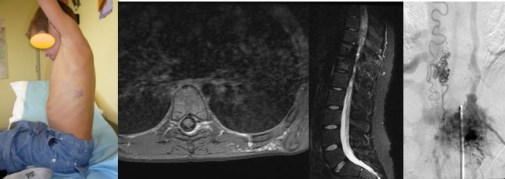

le sinus pericranii

il s’agit d’une communication tans-osseuse entre les veines intra et extra-crâniennes. il existe parfois une vaste poche sous-cutanée qui peut nécessiter une résection chirurgicale.

le sinus pericranii peut se thromboser spontanément